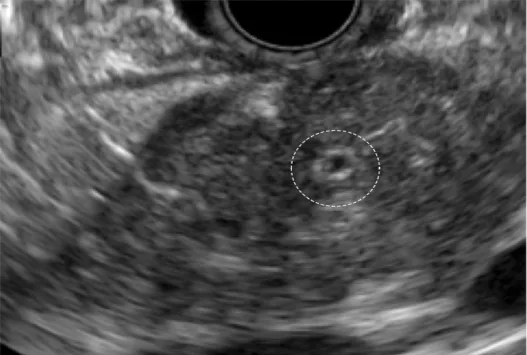

Quels sont les signes écho-­endoscopiques évocateurs de PAI ? (Figs 11- 14)

1) La ductite : c’est l’association d’un remaniement important du calibre du canal pancréatique principal (CPP), alternant des segments où il est sténosé (sténose longue) mais encore repérable, collabé, et des segments où il est normal voir dilaté (> 3 mm mais < 5 mm de diamètre), et d’un épaississement hyperéchogène ou hypoéchogène (comparé au parenchyme avoisinant) de sa paroi.

Point essentiel, cet aspect est retrouvé à la fois dans la forme diffuse (hypertrophiante classique ou atrophique plus rare) et dans la forme focale pseudo-tumorale, on parle alors de « penetrating sign » ce qui correspond à la mise en évidence du canal sténosé ou collabé, mais visible dans la pseudo tumeur, signe exceptionnellement retrouvé dans l’adénocarcinome pancréatique. Dans notre expérience, dans une étude cas/contrôle effectuée à l’hôpital Beaujon [21] comparant des PAI absolument certaines, des cancers du pancréas et des pancréatites chroniques classiques, la sensibilité et la spécificité de ce signe étaient très élevées (> 90 %). L’épaississement hyperéchogène de la paroi (Fig. 12) était plus souvent observé dans la PAI de type I, tandis que l’épaississement hypoéchogène (Fig. 13) était surtout observé dans la PAI de type II.

2) La cholangite : c’est l’épaississement supérieur à 1 mm de la paroi de la voie biliaire principale (Fig. 14). Elle était observée une fois sur deux (de manière quasi constante dans les pancréatites auto-immunes avec ictère), 7 fois sur 10 en cas de PAI de type I et une fois sur trois dans la PAI de type II. Lorsqu’il dépasse 2 mm cet épaississement est hautement évocateur d’une PAI de type I.

Figure 11. Aspect échoendoscopique caractéristique d’une PAI. Noter la tuméfaction de la région corporéo-caudale et les sténoses multiples du CPP, qui sont superposables à l’aspect macroscopique de la figure 4